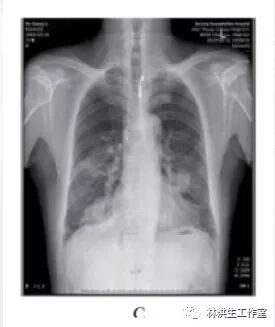

A: 2013 年 8 月 23 日发病时,胸部 CR 片显示双侧肺肿物;